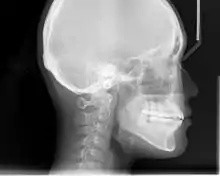

Lateral cephalometric radiographs

Lateral cephalometric radiograph, used for skull analysis

Lateral cephalometric radiograph is a radiograph of the head taken with the x-ray beam perpendicular to the patient's sagittal plane. Natural head position is a standardized orientation of the head that is reproducible for each individual and is used as a means of standardization during analysis of dentofacial morphology both for photos and radiographs. The concept of natural head position was introduced by Coenraad Moorrees and M. R Kean in 1958[9][10] and now is a common method of head orientation for cephalometric radiography.[11][12]

Registration of the head in its natural position while obtaining a cephalogram has the advantage that an extracranial line (the true vertical or a line perpendicular to that) can be used as a reference line for cephalometric analysis, thus bypassing the difficulties imposed by the biologic variation of intracranial reference lines. True vertical is an external reference line, commonly provided by the image of a free-hanging metal chain on the cephalostat registering on the film or digital cassette during exposure. The true vertical line offers the advantage of no variation (since it is generated by gravity) and is used with radiographs obtained in natural head position.